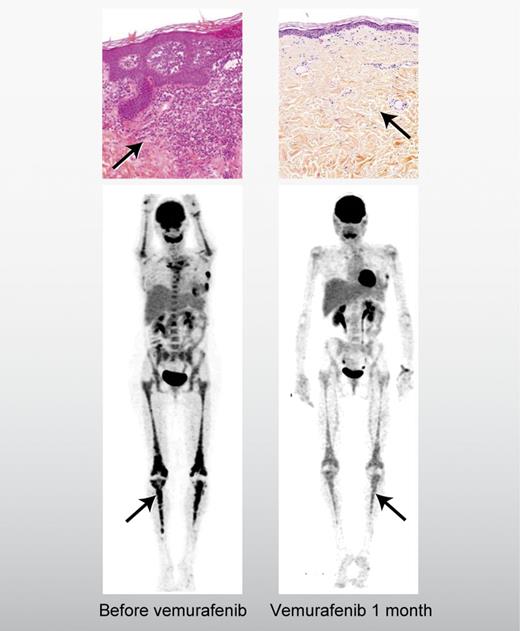

Saving orphans: BRAF targeting of histiocytosis. A patient with Langerhans cell histiocytosis in the skin (top panels) and Erdheim-Chester disease in the long bones (bottom panels) before and after treatment with vemurafenib.1 Professional illustration by Alice Y. Chen.

Haroche et al have tested the notion that the BRAF V600E acts as a so-called “driver mutation” of these diseases by treating 3 patients with refractory ECD, 2 of whom had coincident LCH, with vemurafenib, which was recently approved for use in patients with metastatic melanoma characterized by BRAF V600E mutation.1,6 The responses in ECD and LCH were, in the words of the authors, “dramatic.” Two of the 3 patients had symptomatic improvement within days of the initiation of vemurafenib and all 3 patients had significant disease regression after a few weeks of treatment. In the 2 patients who had both LCH and ECD, there was clinical response in both histiocytic conditions. It should be noted that vemurafenib was not without toxicity and all 3 patients required a reduction from the initial dose due to rash, a common side-effect. Further, the dramatic nature of the results must be tempered against the small size of the case series and the short follow up. Median progression-free survival in patients with vemurafenib-treated melanoma was less than 6 months, so the duration of response in the histiocytosis patients will continue to be a point of interest.6